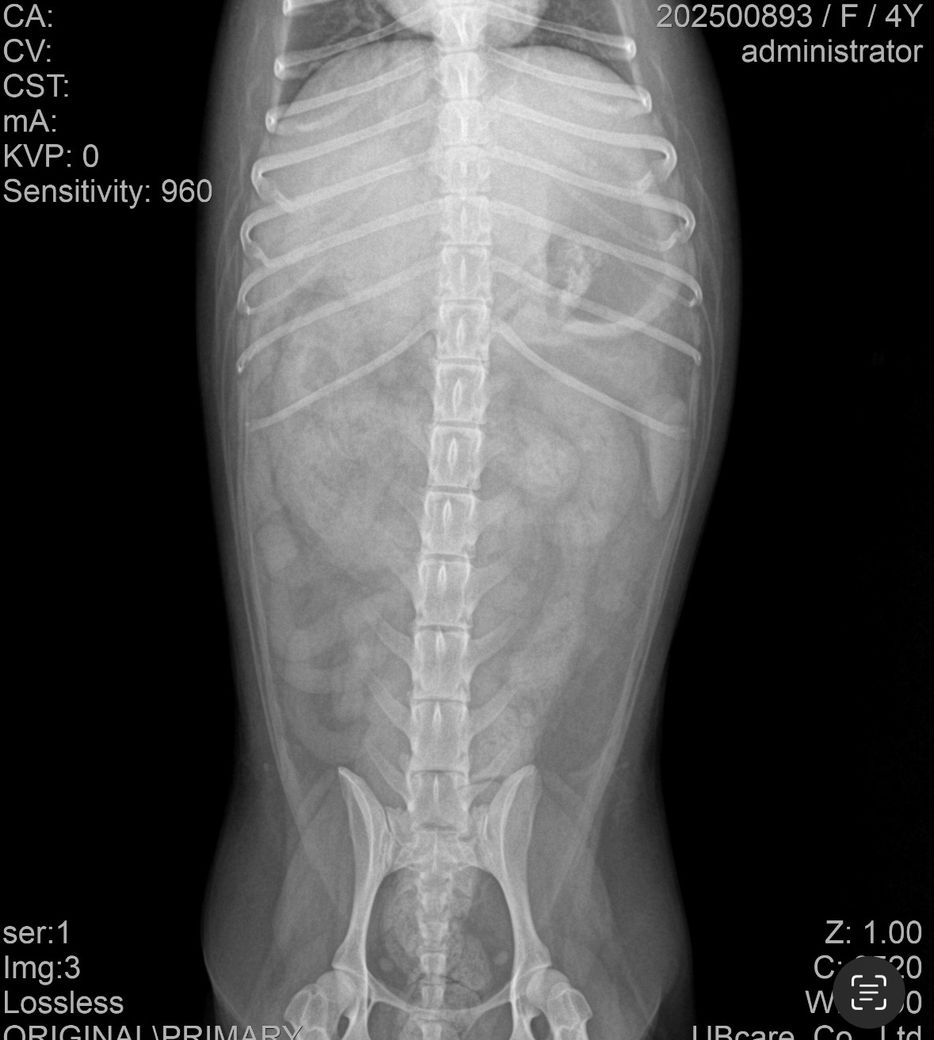

• 엑스레이, 초음파 검사 진행

• 검사 결과: 이물 가능성 있음, 확실하지 않음

4. 첨부 엑스레이에서 이물 여부 확인 가능 여부

엑스레이에서는 명확한 이물이 보이지 않을 수 있습니다. 플라스틱, 실, 천조각처럼 방사선 불투과성이 낮은 이물은 거의 보이지 않기 때문에 초음파로 확인하거나, 장 내 액체 정체나 장 운동 저하로 간접적으로 의심하는 경우가 많습니다. 물을 마셔도 바로 토하는 패턴은 위에서 내용물이 내려가지 못하거나, 위 자체가 심하게 자극된 상황에서 흔히 나타나며 이물 가능성과 위염 두 가지 모두에서 보일 수 있습니다.

첨부한 사진은 복배상의 사진밖에 없고 외측상이 없어 판독할 수 없습니다. 방사선 사진은 원래 앞사진, 옆사진 이렇게 최소 2장이 필요합니다.